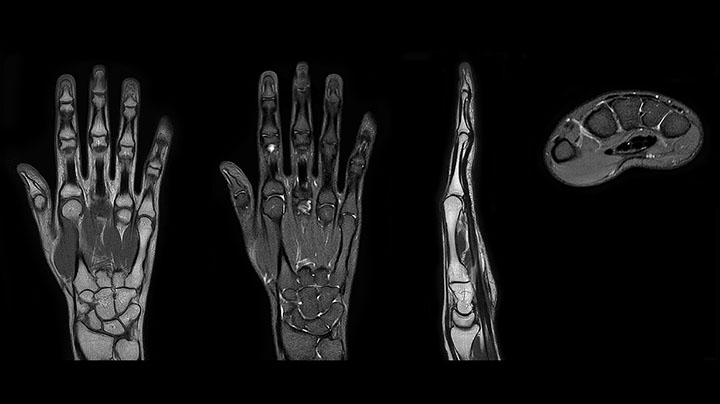

Bildgebung der Hand mit Prodiva deckt die Fingerspitzen und das gesamte Handgelenk ab. Die dS MSK M Spule ist anwenderfreundlich.

MRT des Fingers mit hohem SNR und guter Auflösung in einem 10-cm-Sichtfeld auf Prodiva 1.5T. Die Diagnose bei diesem 63-jährigen Patienten lautet Knochenelasmanose.